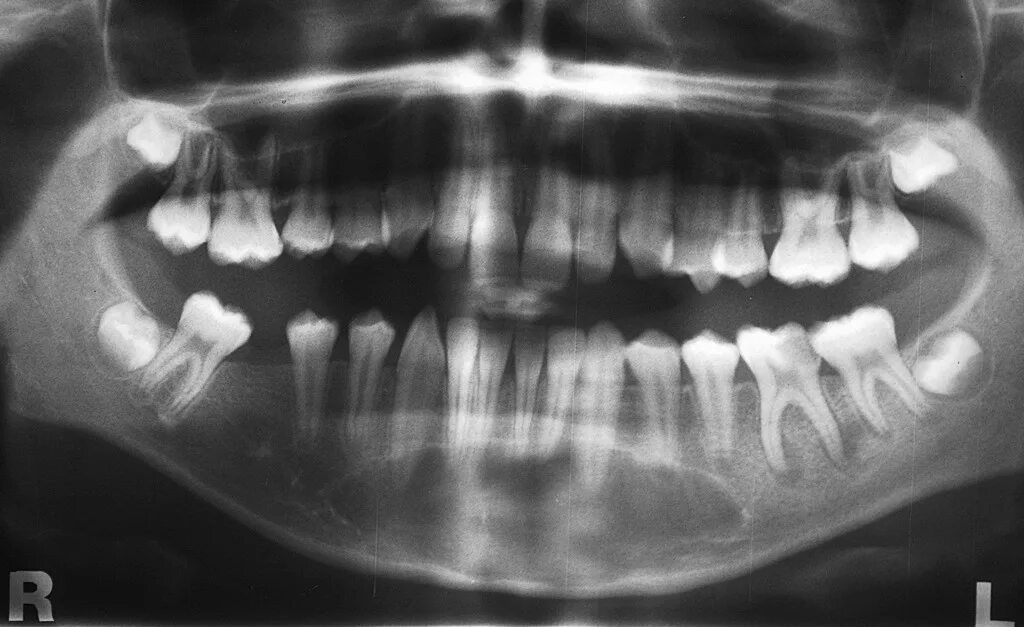

Киста зуба что это